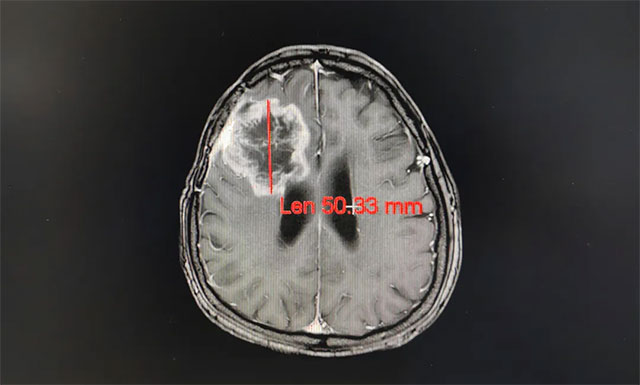

完善其各項檢查,王曉東主任根據(jù)姚女士的臨床資料、病理診斷和影像結(jié)果,確定患者滿足放療條件,并制定了完善周密的放療計劃。之后患者進行了一個療程(30次)的放射治療,放療期間未見明顯不良反應(yīng),經(jīng)過放射治療,姚女士的病灶由原來的61.52mm縮小到50.33mm;其頭痛、惡心癥狀明顯改善,大小便也恢復(fù)正常,走路不穩(wěn)的癥狀也得到了緩解。

▲ 經(jīng)過放射治療患者病灶變小,其癥狀明顯改善